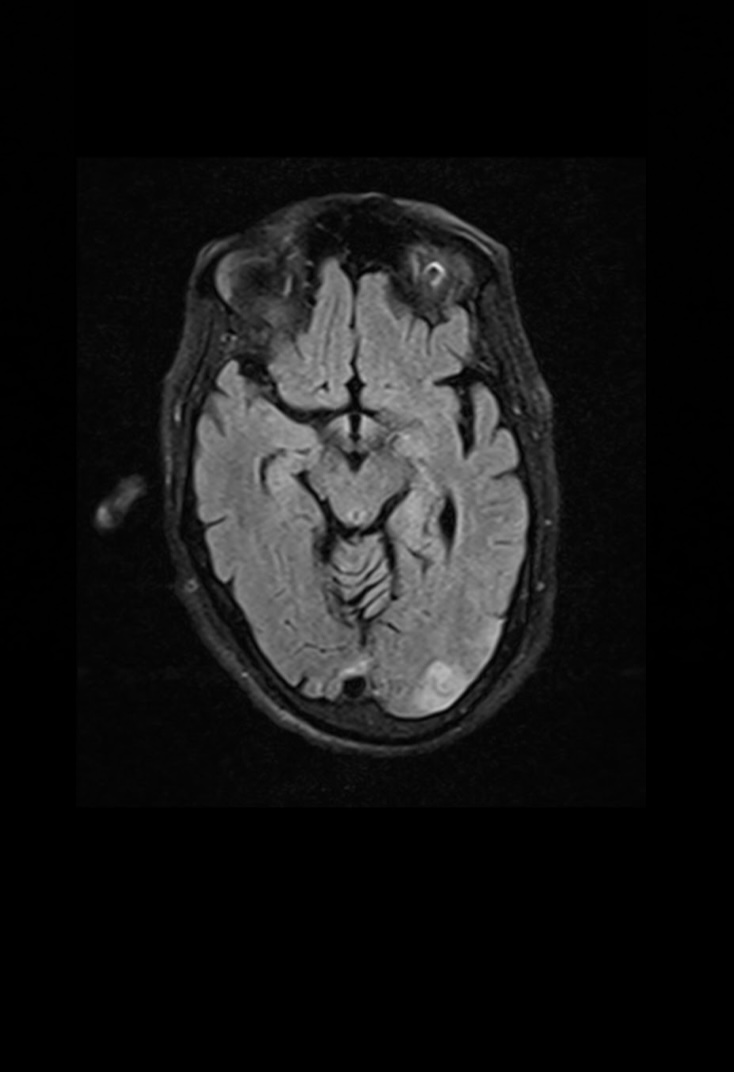

Provisional diagnosis -

CEREBRAL VASCULAR DAMAGE

ATHEROSCLEROSIS